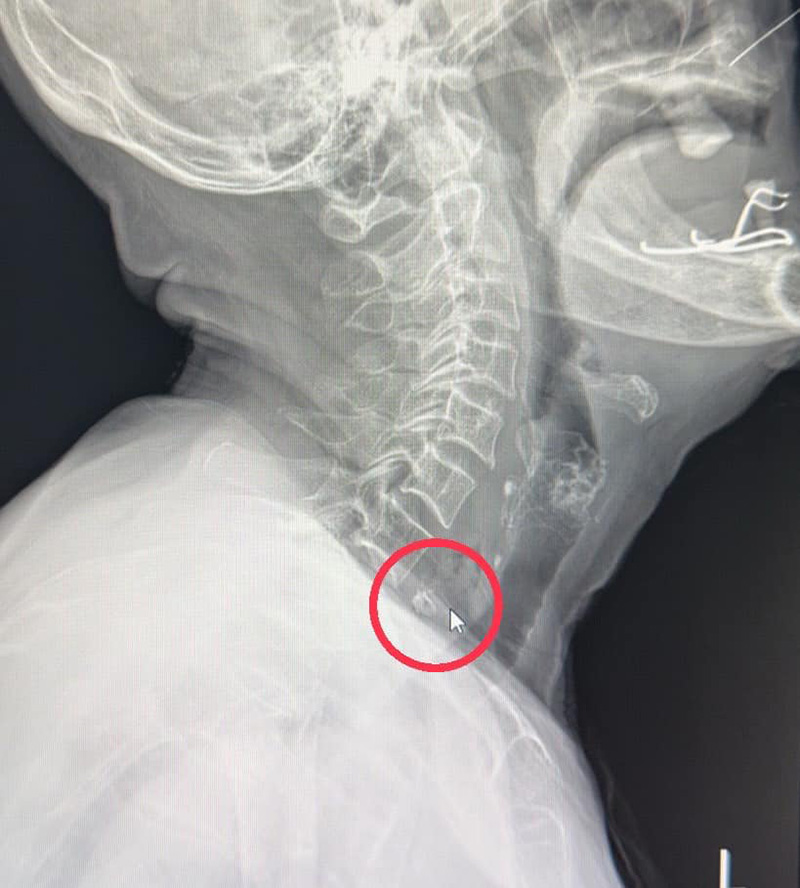

เบื้องต้น แพทย์ใช้เครื่องมือส่องหลอดลมก็มองไม่เห็น จึงส่งเอกซเรย์พบเห็นเป็นก้อนเนื้อปนเศษกระดูกชิ้นเล็ก ๆ ในส่วนลึกของลำคอ จึงปรึกษาแพทย์ผู้เชี่ยวชาญด้านหูคอจมูก เตรียมความพร้อมเข้าห้องผ่าตัดฉุกเฉิน

แพทย์ได้ใช้เครื่องส่องกล้องในหลอดอาหาร พบก้อนเนื้อนกสับขนาด 3.5 เซนติเมตร ติดแน่นที่หลอดอาหารส่วนบนและเบียดหลอดลมอยู่ แพทย์จึงใช้เครืองมือผ่าตัดสอดใส่ผ่านกล้อง คีบออกมาได้สำเร็จ

พบว่ามีชิ้นส่วนกระดูกที่มีคม ทิ่มแทงผนังหลอดอาหารจนเป็นแผลมีเลือดไหล หลายจุด หลังผ่าตัดต้องให้ยาต้านเชื้อระงับการอักเสบติดเชื้อตามมา โดยผู้ป่วยนอนในโรงพยาบาล 3 วัน กลับบ้านได้ ปลอดภัย ไม่มีภาวะแทรกซ้อนของสิ่งแปลกปลอมมีคมติดค้างในหลอดอาหาร